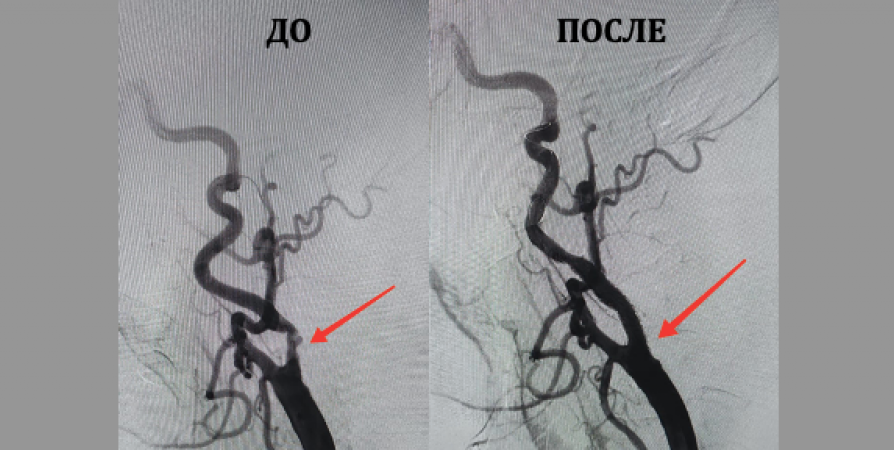

- УЗИ сосудов шеи пациента показало стенозы и атеросклеротические бляшки в сонной артерии пациента. Ангиографическое исследование подтвердило, что сосуды шеи «забиты» и риск инсульта крайне высок, - рассказал врач-ангиохирург, заместитель директора по высоким медицинским технологиям ММЦ имени Н.И.Пирогова ФМБА России Михаил Воронин.

Он объяснил, что левое и правое полушария головного мозга снабжаются сонными артериями. При ее атеросклеротическом поражении возникает высокий риск эмболии - когда частички атеросклеротической бляшки с кровотоком попадают в головной мозг.